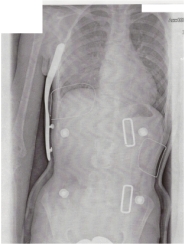

gestern waren wir beim röntgen im korsett und es sitzt perfekt

(das ergebnis gibt´s unten)